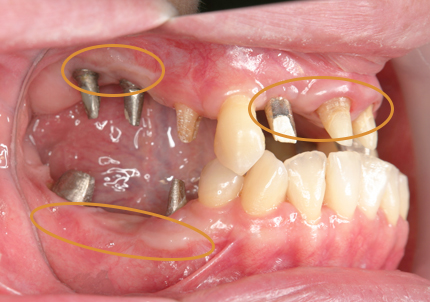

13.下顎補綴治療開始(2016年1月9日)

14.インプラント埋入(2016年8月24日)

16.下顎インプラント補綴治療終了(2017年4月8日)